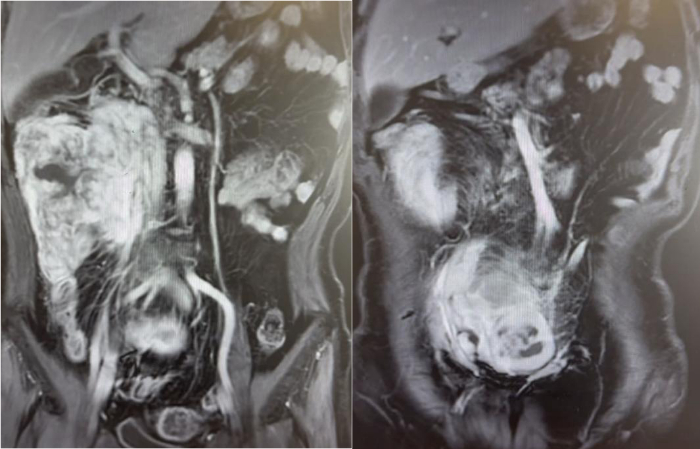

63岁男性,腹膜后脂肪肉瘤术后2年,肿瘤复发3个月。因复发肿瘤导致肠梗阻已无法进食。

我们为患者实施了全麻下开放腹腔肿物切除+回肠部分切除+右侧腹膜后肿物切除+右肾切除+右半结肠切除手术,手术历时2小时,出血200ml以内。术后第1天下地,术后4天排气,术后1周流食,术后10天出院。